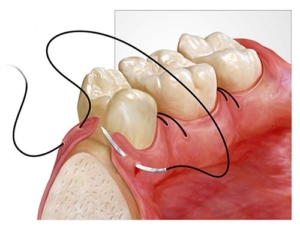

- بعد از جراحی لثه ؛دندانپزشك لثه را بخیه نموده و برای حفاظت موضع از تحریكات؛با استفاده از خمیر پانسمان آنجا میپوشاند.توجه داشته باشید كه از برداشتن و دستكاری آن با دست و زبان خودداری نمایید.در ضمن جدا شدن تكه ای از آن مهم نیست.

- در روز اول بعد از جراحی از دهانشویه استفاده نكنید و مسواك هم نزنید. از روز بعد مسواك زدن را آغاز نموده و در صورت تجویز میتوانید از دهانشویه استفاده كنید.در صورت استفاده از دهانشویه از آن به ملایمت استفاده نمایید.

- پس از برداشته شدن پانسمان و كشیدن بخیه ها میتوانید دندانهای ناحیه عمل شده را با مسواك و به آرامی تمیز نمایید.ممكن است در روزهای اول و شروع مسواك زدن ناحیه عمل شده؛لثه خونریزی داشته باشد كه عادی است.تمیز كردن را به خاطر آن متوقف نكنید.